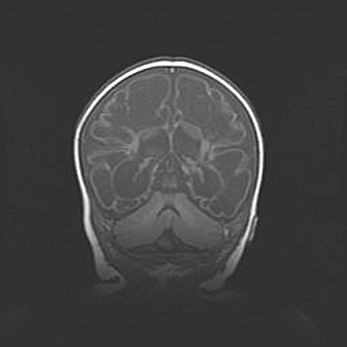

Наружная гидроцефалия с возможной атрофией височных областей.

Возраст: 28 дней

Вес: 3670 г

Пол: мужской

Окружность головы: 38 см

Срок гестации: 40 недель

Гидроцефалия головного мозга у новорожденных – это заболевание, которое характеризуется скоплением избыточного количества спинномозговой жидкости в желудочковой системе головного мозга в результате затруднения её перемещения от места выработки к месту поглощения в кровеносную систему или вследствие нарушения абсорбции. При открытой наружной форме гидроцефалии у новорожденных расширяются и переполняются субарахноидные пространства.

При нормотензивных  формах,  которые,  как  правило,  являются  следствием  перенесенных ишемических  повреждений  паренхимы  мозга,  возможно  сочетание микроцефалии  с нормотензивной гидроцефалией. В основе данных изменений лежит атрофия больших полушарий с преимущественной  локализацией  в  лобно-височных  областях.